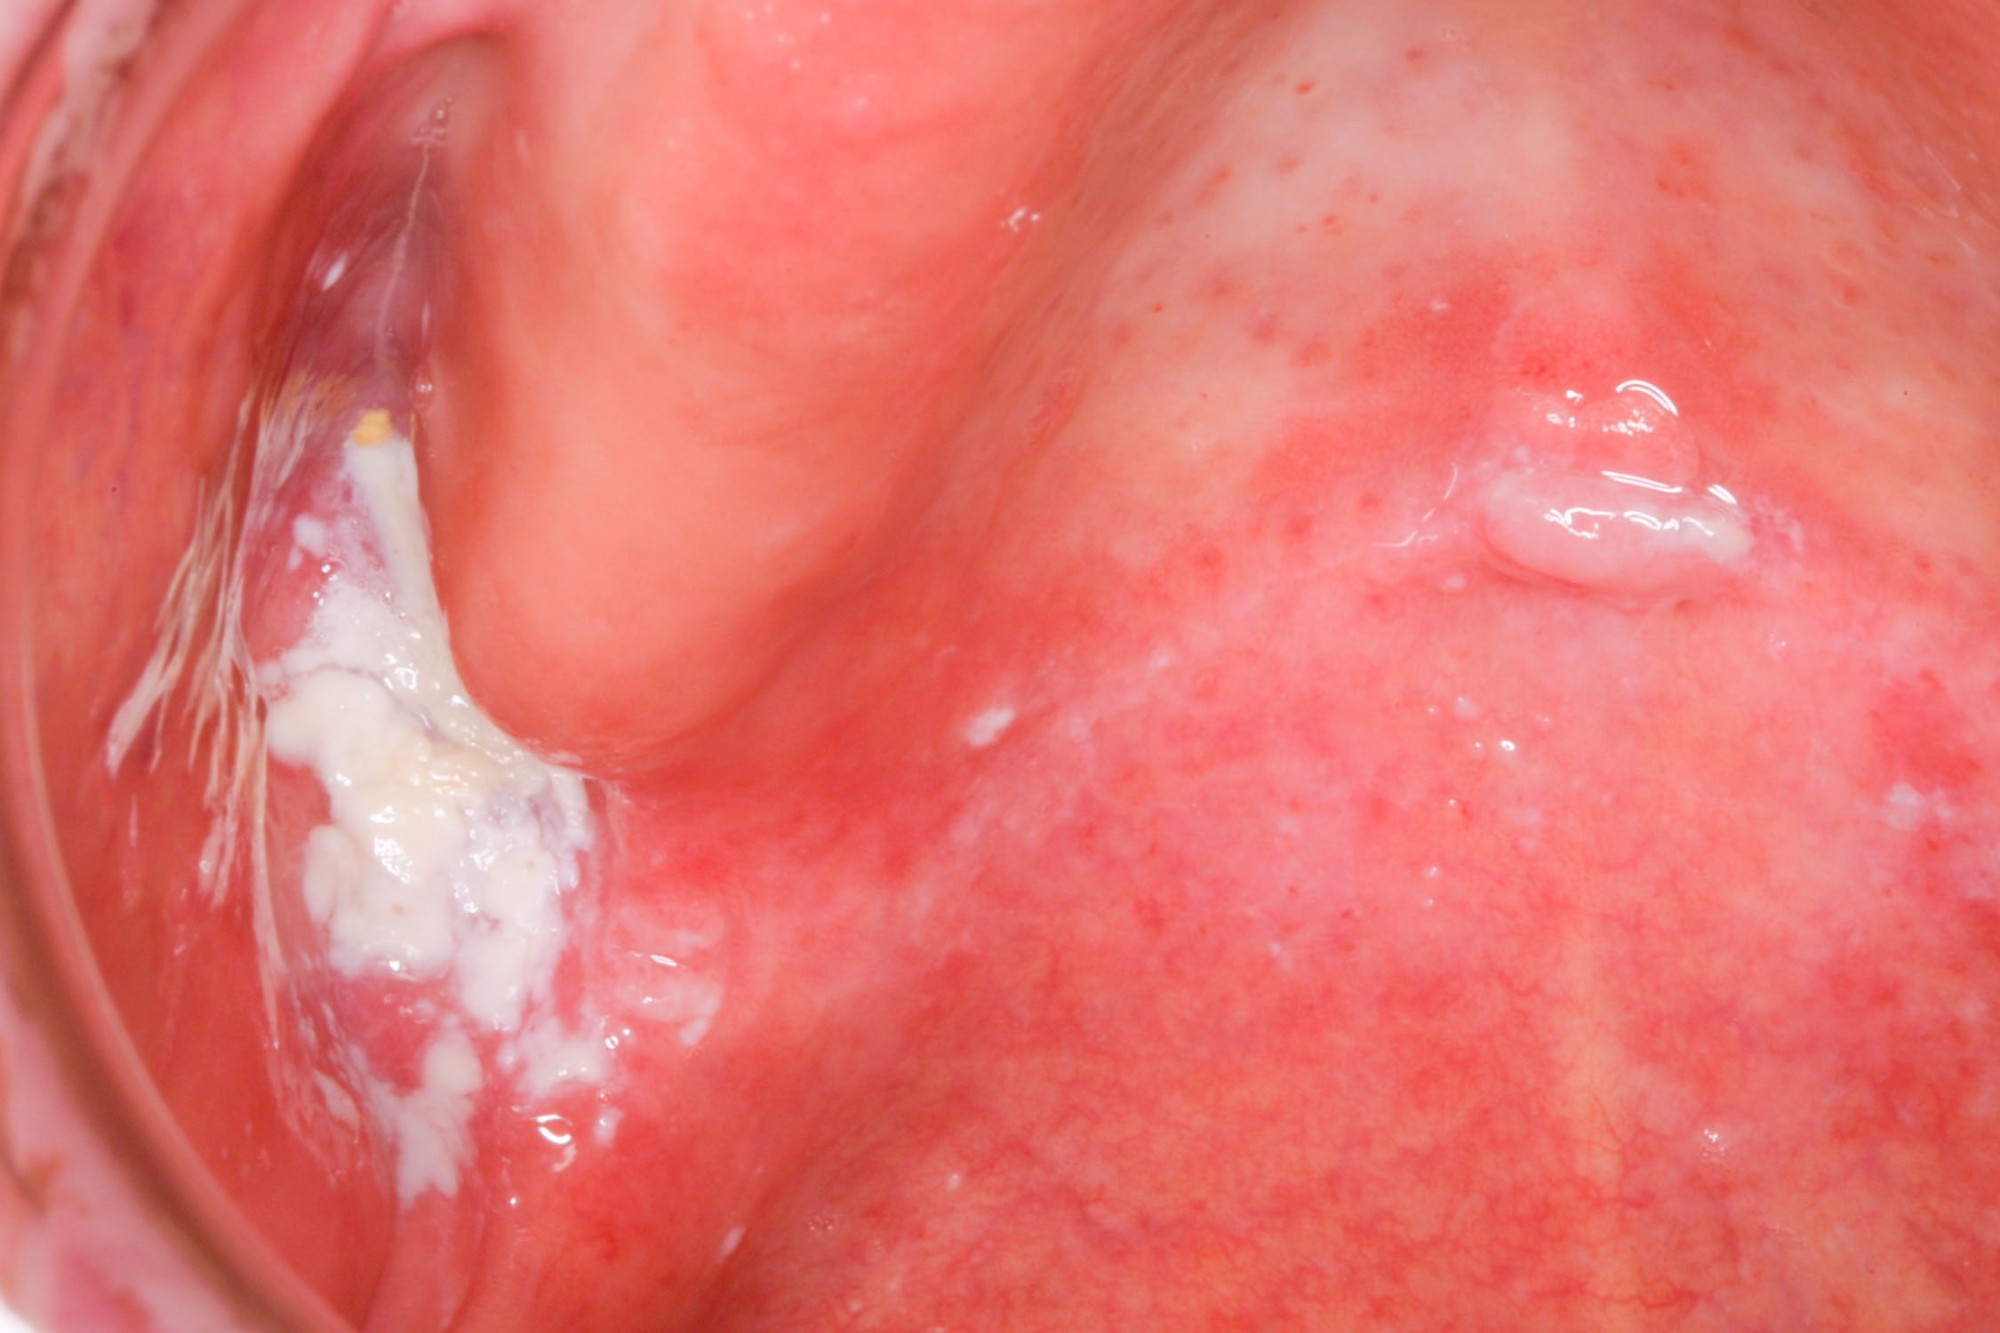

Borken

Borken sind verkrusteter Schleim und ebenfalls ein Zeichen für Mundtrockenheit. Gerade im Bereich der Prothesenauflageflächen können Borken auch mit Haftcremeresten verwechselt werden oder mit diesen vermengt sein. In jedem Fall sollte zunächst die Pflege der Mundschleimhäute und Zahnprothesenpflege intensiviert werden.

Beispiele4 Bilder